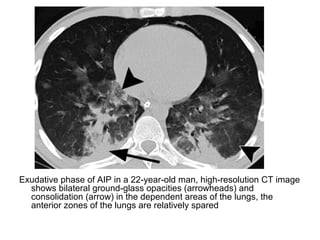

Exudative phase of AIP in a 22-year-old man, high-resolution CT image

shows bilateral ground-glass opacities (arrowheads) and

consolidation (arrow) in the dependent areas of the lungs, the

anterior zones of the lungs are relatively spared